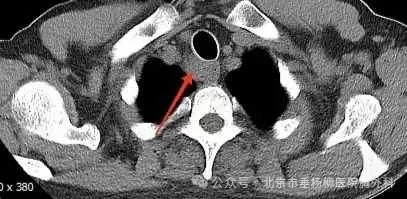

胸部CT(纵隔窗)

患者男性,60岁,主因“发现纵隔肿物9天余。”来诊。患者自述9天前因吞咽食物不适感查胸部增强CT,发现上纵隔气管右后方占位,大小约22*24mm,边界欠清,增强扫描不均匀强化,局部气管、食管受累,恶性待排,双肺及纵隔未见肿大淋巴结,未见胸腔积液,后完善胸部增强核磁:上纵隔气管右后方占位不均匀强化,局部气管、食管受累恶性病变待排,必要时穿刺活检;遂于当地医院依次行气管镜、胃镜检查,结果提示:气管上段右后侧壁外压型改变并管腔轻度狭窄;食管管腔通畅,未见异常隆起及异常外压改变,均未取到有效的病理结果。